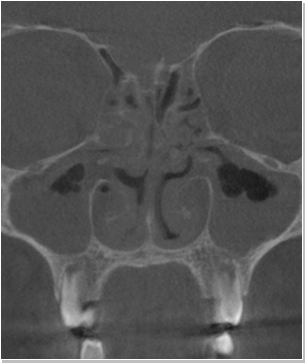

비염

비중격만곡증

축농증